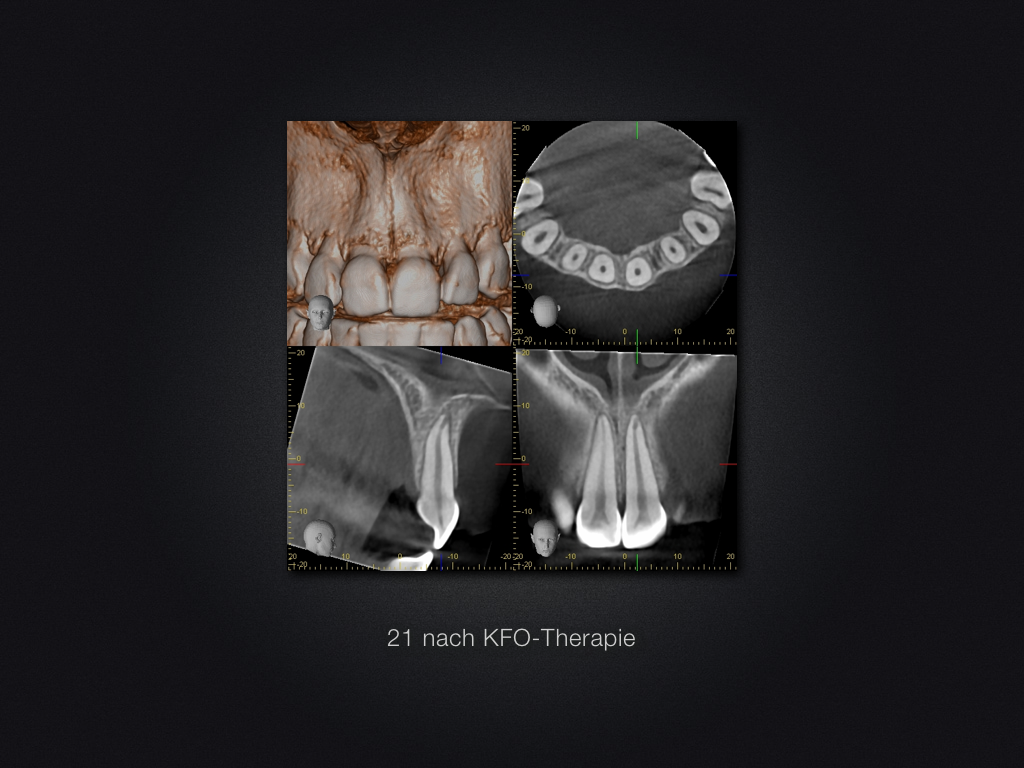

Interne Resorption nach KFO-Therapie